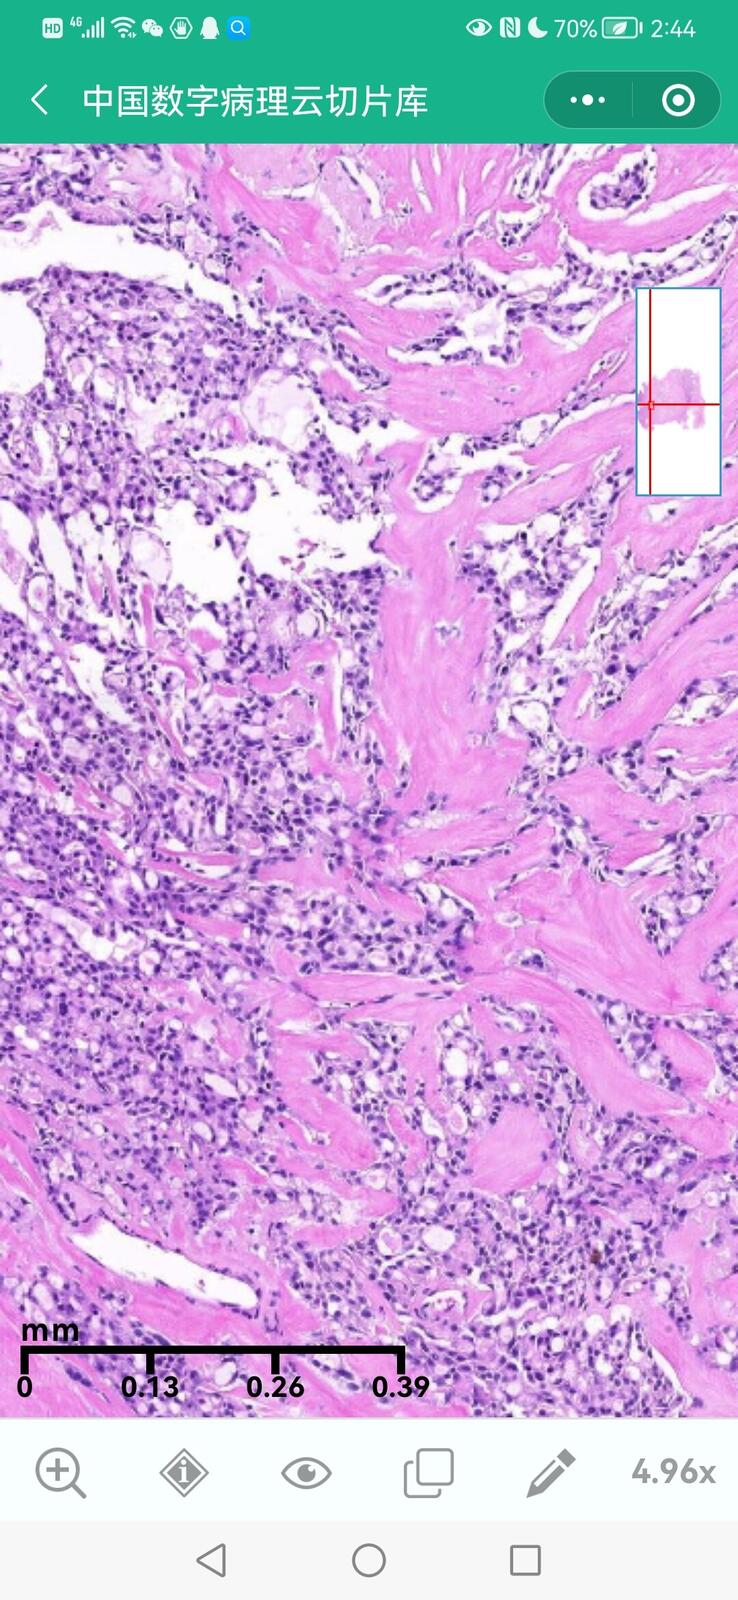

乳腺黏液性囊腺瘤伴导管内癌

乳腺分泌性癌(29岁)